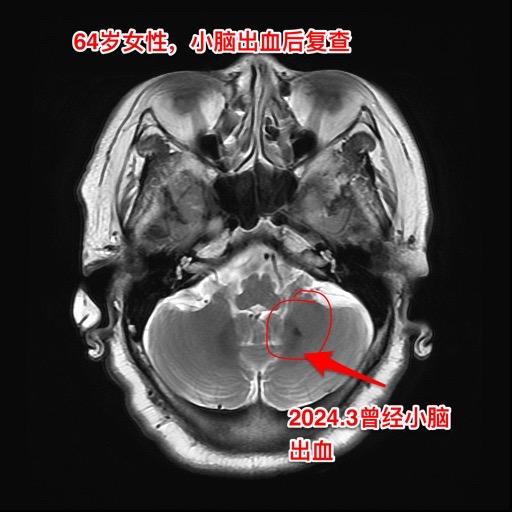

脑血管病很常见,预防胜于治疗。缺血性脑血管病很常见,致死致残,危害性极...